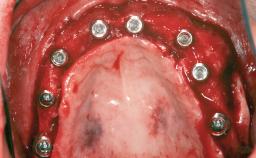

| # of Implants | 8 |

| Bone Augmentation | Horizontal|Sinus Floor Elevation|Staged|Vertical |

| Augmentation Materials | Autogenous chips|Autogenous block(s) |